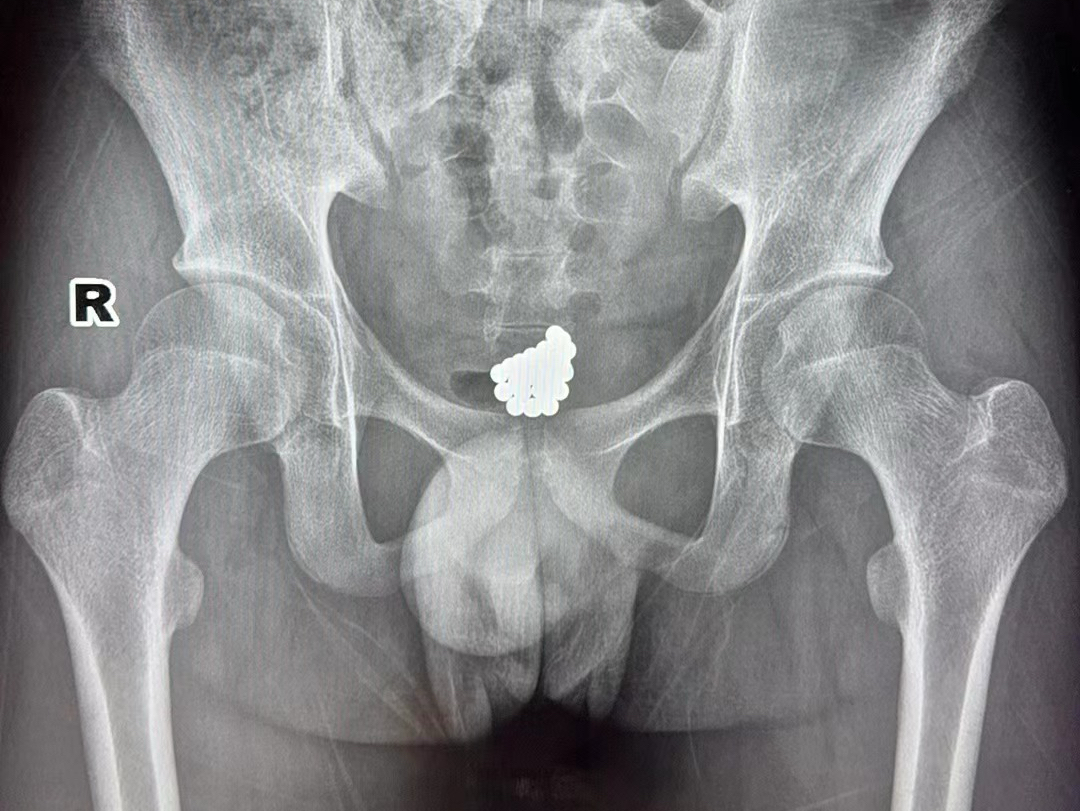

经过初步检查,小杰的尿道口呈现红肿的情况。随后,小杰又到放射科进行了详细检查。这一查,让在场的医生也不禁一愣,一坨小珠子堆积在小杰的盆腔区域,看样子还不少啊。

小杰的影像检查图